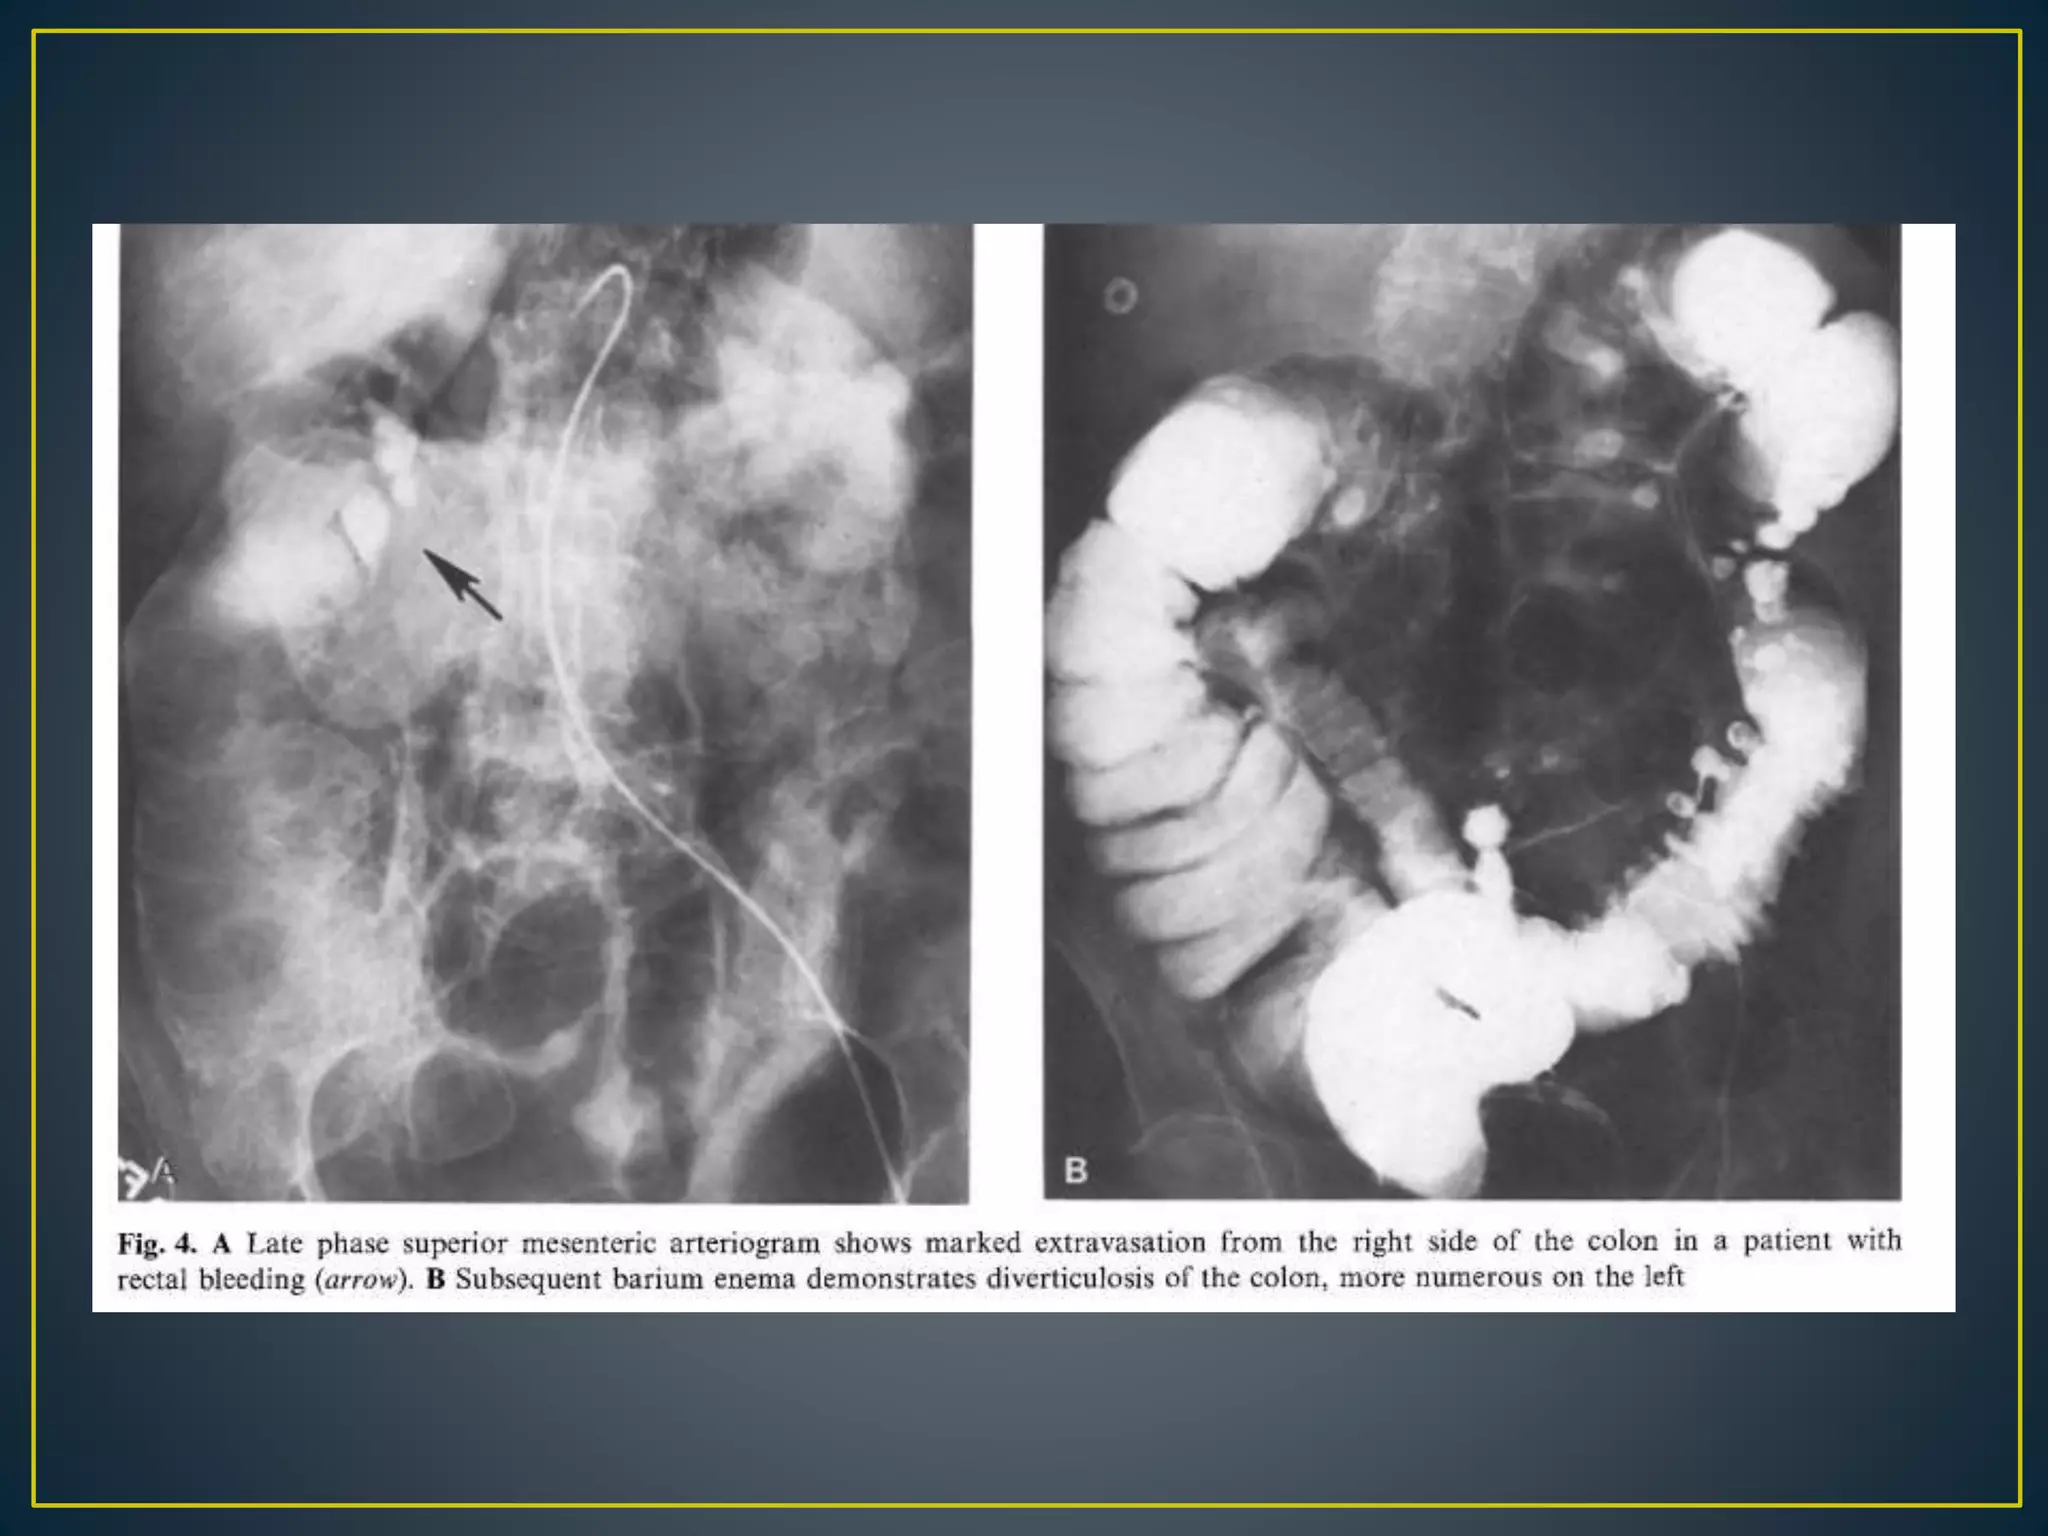

• Diverticulosis Has been implicated as the source of

bleeding in as many as 60% of cases of lower GI

bleeding.

• The diverticula are more prevalent in the left or sigmoid

colon, but positive arteriography findings for bleeding

localizes the bleeding to the right colon in 60% of cases

• Diverticular bleeding does not have a characteristic

appearance unless contrast fills the diverticulum itself